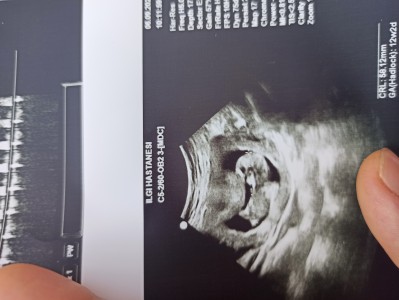

Arkadaşlar 12+1tahmin yapar mısınız

Gebelik haftası 12+